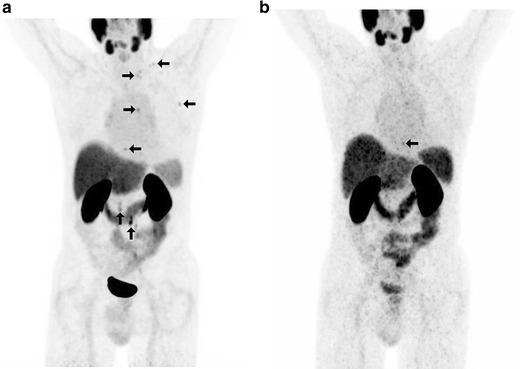

In 14 selected patients with PSA relapse of prostate cancer, [(18)F]DCFPyL PET/X-ray computed tomography (CT) was performed in addition to [(68)Ga]Ga-PSMA-HBED-CC PET/CT. A systematic comparison was carried out between results obtained with both tracers with regard to the number of detected PSMA-positive lesions, the standardized uptake value (SUV)max and the lesion to background ratios.

RESULTS

All suspicious lesions identified by [(68)Ga]Ga-PSMA-HBED-CC were also detected with [(18)F]DCFPyL. In three patients, additional lesions were observed using [(18)F]DCFPyL PET/CT. The mean SUVmax in the concordant [(18)F]DCFPyL PSMA-positive lesions was significantly higher as compared to [(68)Ga]Ga-PSMA-HBED-CC (14.5 vs. 12.2, p = 0.028, n = 15). The mean tumor to background ratios (n = 15) were significantly higher for [(18)F]DCFPyL compared to [(68)Ga]Ga-PSMA-HBED-CC using kidney, spleen, or parotid as reference organs (p = 0.006, p = 0.002, p = 0.008), but no significant differences were found using the liver (p = 0.167) or the mediastinum (p = 0.363) as reference organs.

在14例选定的前列腺癌PSA复发患者中,除了进行[(68)Ga]Ga-PSMA-HBED-CC PET/CT外,还进行了[(18)F]DCFPyL PET/X射线计算机断层扫描(CT)。对两种示踪剂获得的结果在检测到的PSMA阳性病变数量、标准化摄取值(SUV)最大值和病变与背景比值方面进行了系统比较。

结果

[(68)Ga]Ga-PSMA-HBED-CC识别出的所有可疑病变也能用[(18)F]DCFPyL检测到。在3例患者中,使用[(1)F]DCFPyL PET/CT观察到了额外的病变。与[(68)Ga]Ga-PSMA-HBED-CC相比,[(18)F]DCFPyL PSMA阳性病变中的平均SUV最大值显著更高(14.5对12.2,p = 0.028,n = 15)。以肾脏、脾脏或腮腺作为参考器官时,[(18)F]DCFPyL的平均肿瘤与背景比值(n = 15)显著高于[(68)Ga]Ga-PSMA-HBED-CC(p = 0.006,p = 0.002,p = 0.008),但以肝脏(p = 0.167)或纵隔(p = 0.363)作为参考器官时未发现显著差异。